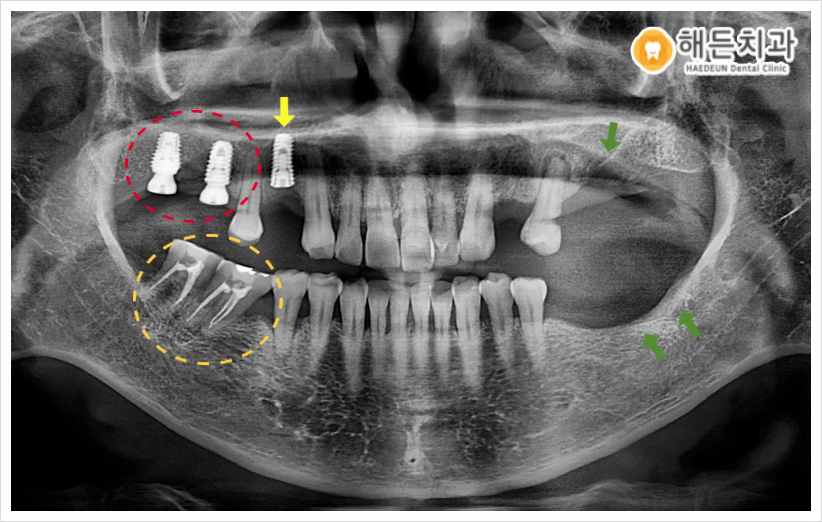

오늘 소개해 드릴 분께서는 빨간색 동그라미 표시의, 오른쪽 위턱 어금니 부위의 임플란트 치료를 원하셨는데요. 치주 질환으로 인해 잇몸 건강이 나빠지면서 어금니 치아를 상실하게 되었다고 말씀해 주셨습니다.

파노라마사진을 촬영하여 검사해 보았더니, 환자분께서 치료를 원하시는 부위를 제외하고도 문제가 있는 치아들을 다수 확인할 수 있었는데요.

✔ 노란색 화살표의 오른쪽 위턱 첫 번째 작은 어금니(#14) 주변으로 잇몸뼈가 많이 녹아 동요도가 심하여, 발치가 필요한 상황이었습니다.

✔ 그리고 주황색 동그라미의 오른쪽 아래턱 어금니 부위에는 첫 번째 큰 어금니(#46)가 상실한 상태라, 나머지 두 어금니(#47,48)가 첫 번째 큰어금니 자리로 많이 기울어져 있었으며 위에 맞물리는 어금니가 없다 보니 위로 솟구쳐 올라와 있었습니다.

✔ 또한 왼쪽 위아래 어금니 부위도 주변 치아 상실로 인해 치아가 많이 기울어져 있었으며 주변 잇몸 상태도 많이 안 좋아 동요도가 있는 상황으로, 발치가 필요한 상태였습니다.